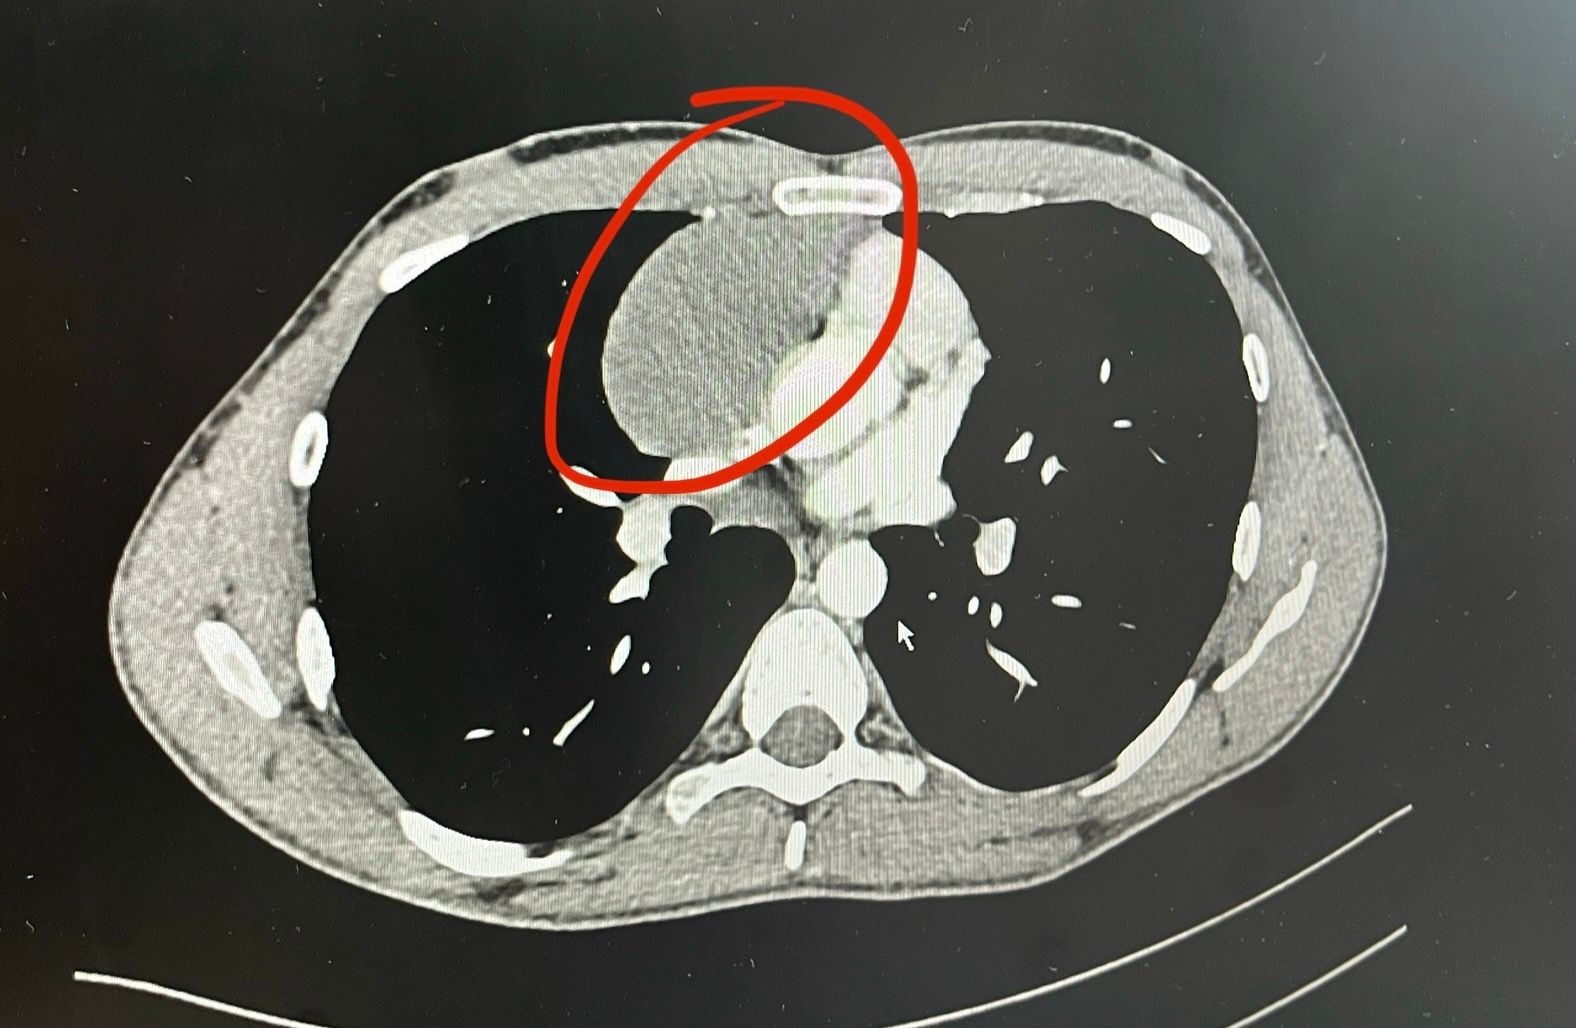

Just over a year ago, a tangerine sized tumor was found next to my heart.

Thanks to God, my doctors and nurses, and the Korean healthcare system, I am cancer free today and am able to enjoy this beautiful experience we call life.

I touch on this in my cancer video, but I got extremely lucky. I didn’t have to go through chemotherapy or even radiotherapy. My surgery was a “full resection” — meaning the surgeon removed all of the cancer — and based on the cancer’s Type and Stage, the doctors did not recommend any further treatment.